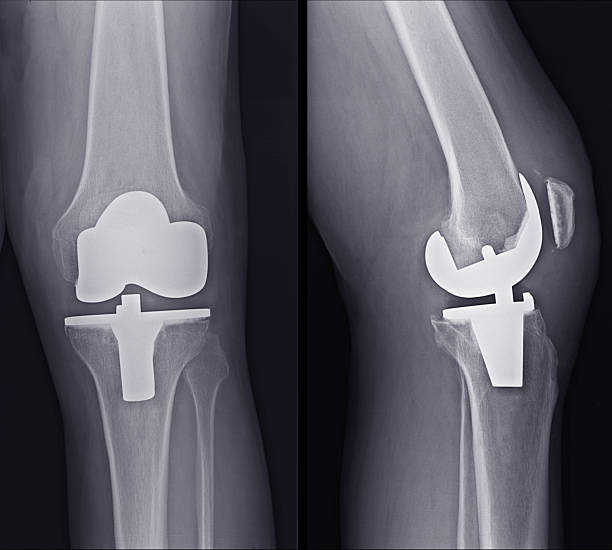

- 대상 질환 : 건강보험급여 '인공관절치환술(슬관절)' 인정기준에 준하는 질환자